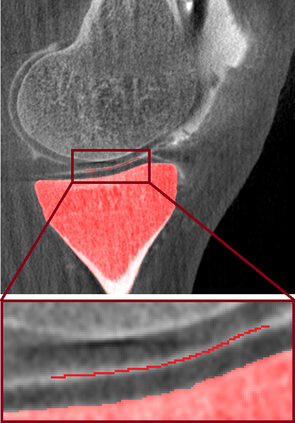

Analyzing knee cartilage thickness and strain under load can help to further the understanding of the effects of diseases like Osteoarthritis. A precise segmentation of the cartilage is a necessary prerequisite for this analysis. This segmentation task has mainly been addressed in Magnetic Resonance Imaging, and was rarely investigated on contrast-enhanced Computed Tomography, where contrast agent visualizes the border between femoral and tibial cartilage. To overcome the main drawback of manual segmentation, namely its high time investment, we propose to use a 3D Convolutional Neural Network for this task. The presented architecture consists of a V-Net with SeLu activation, and a Tversky loss function. Due to the high imbalance between very few cartilage pixels and many background pixels, a high false positive rate is to be expected. To reduce this rate, the two largest segmented point clouds are extracted using a connected component analysis, since they most likely represent the medial and lateral tibial cartilage surfaces. The resulting segmentations are compared to manual segmentations, and achieve on average a recall of 0.69, which confirms the feasibility of this approach.